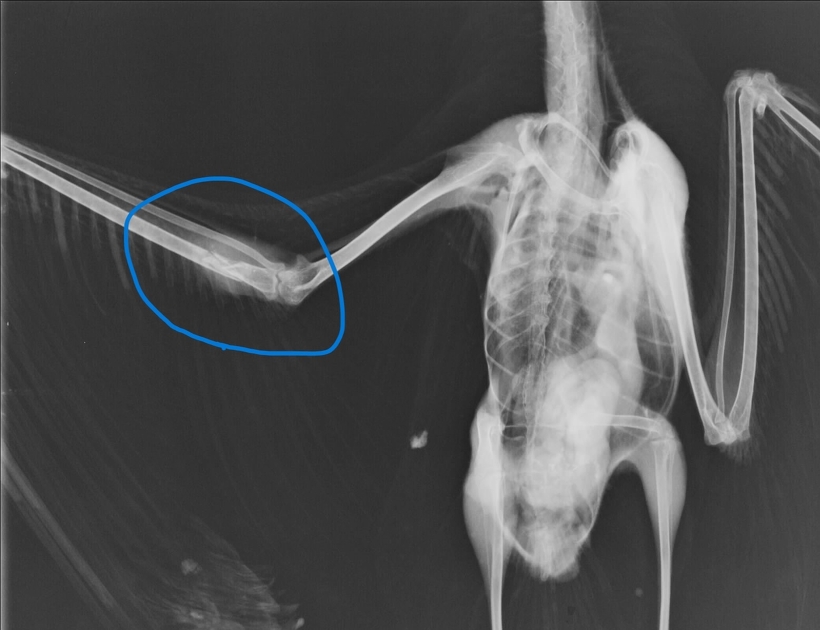

11月2日、はるばる香川県より飛べないウミネコが保護されてやってきました。こちらも左翼の尺骨が骨折していました。